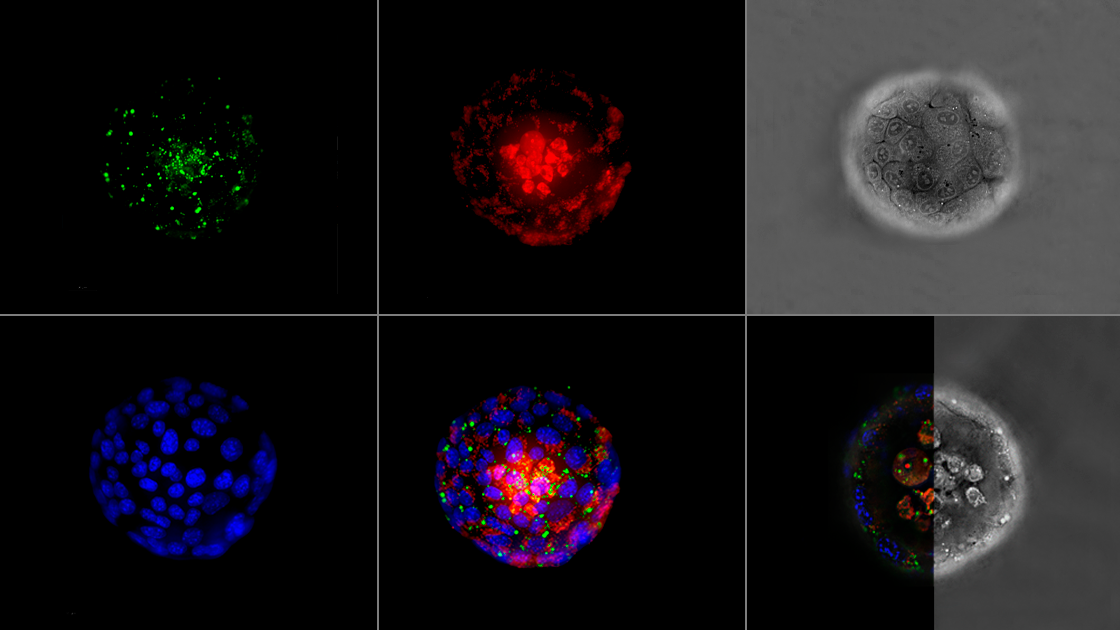

Được trang bị camera thông số kỹ thuật cao với trường nhìn rộng hơn gấp 4 lần và thời gian thu nhận giảm đáng kể, HT-X1 Plus hoàn hảo cho việc sàng lọc kiểu hình tốc độ cao của tế bào và cơ quan nhân tạo. Khả năng tạo ảnh tương quan được nâng cấp – tích hợp mô-đun huỳnh quang dựa trên sCMOS – cho phép kết hợp liền mạch các nghiên cứu phân tử với hình ảnh 3D độ phân giải tế bào đơn.

Kết hợp huỳnh quang tiên tiến

Tối ưu hóa chất lượng hình ảnh 3D bằng cách tích hợp HT với mô-đun huỳnh quang trang bị sCMOS, mang đến khả năng chụp ảnh huỳnh quang 3D tiên tiến.

Hình ảnh huỳnh quang tương quan nâng cao

HT-X1 Plus cung cấp khả năng chụp ảnh đa phương thức nâng cao với mô-đun huỳnh quang (FLX™) tích hợp camera sCMOS được thiết kế đặc biệt để đo cường độ tín hiệu chính xác. Mô-đun FLX™ có độ nhạy cao với huỳnh quang, đạt được tỷ lệ tín hiệu trên nhiễu (SNR) tốt hơn và thời gian phơi sáng ngắn hơn. Điều này cho phép các nhà nghiên cứu thu được thông tin về tính đặc hiệu sinh học phân tử từ các bào quan mục tiêu hoặc cảm biến huỳnh quang, ngay cả trong các mẫu có tín hiệu huỳnh quang yếu, chẳng hạn như phản ứng kháng thể hoặc các mô hình cơ quan khó nhuộm.